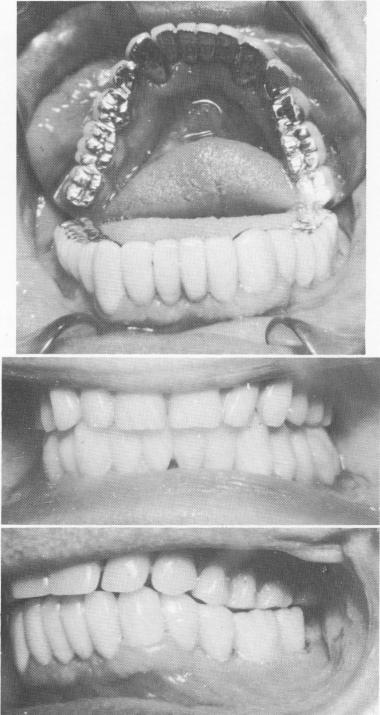

Fig. 13-36. A full arch gold occlusal-acrylic veneer fixed denture was cemented over the endodontically stabilized teeth, with implants adding more support to them.

Fig. 13-37. Intraoral periapical radiographs show the stabilizers and a few of the vent-plants.

2 Gold occlusal acrylic veneer denture on endodontically stabilized teeth

3 Intraoral periapical radiographs show stabilizers & few ventplants